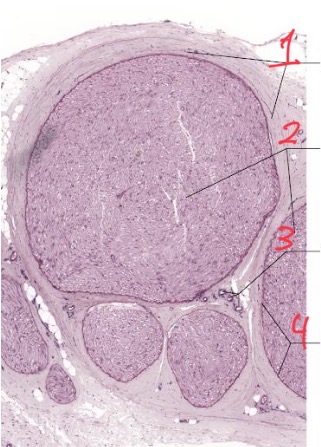

What is this

Peripheral nerve cross section

Peripheral nerve coverings

1

Perineurium

2

Epineurium

3

Endoneurium